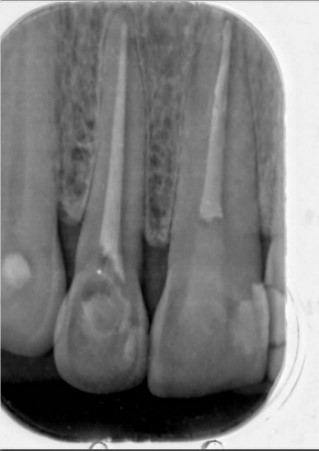

En la figura 2 se observa en la radiografía periapical de la pieza dental #12 la endodoncia en buen estado.

Figura 2. Radiografía periapical